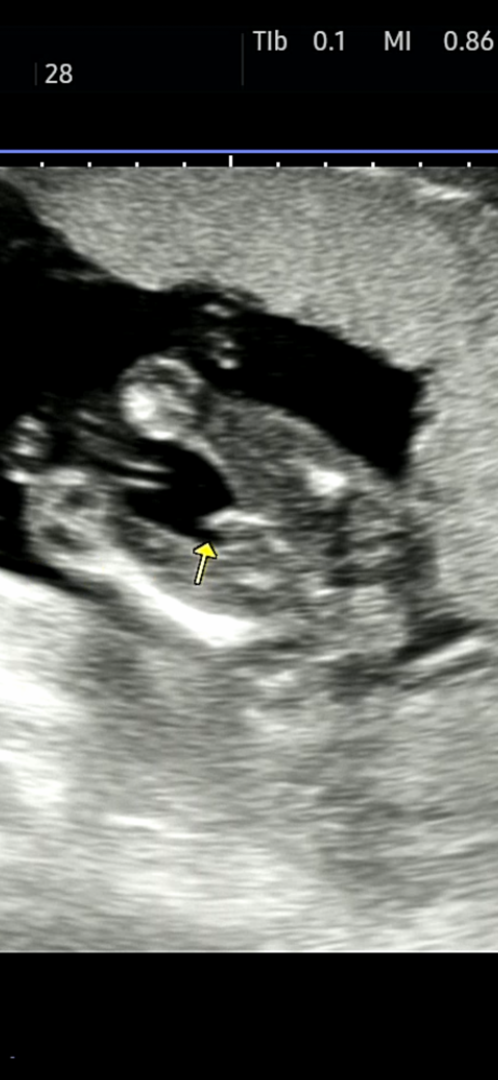

반전은 없겠죠? 딸같았는데 ,, 오늘은 아들 존재감을 보여주네여